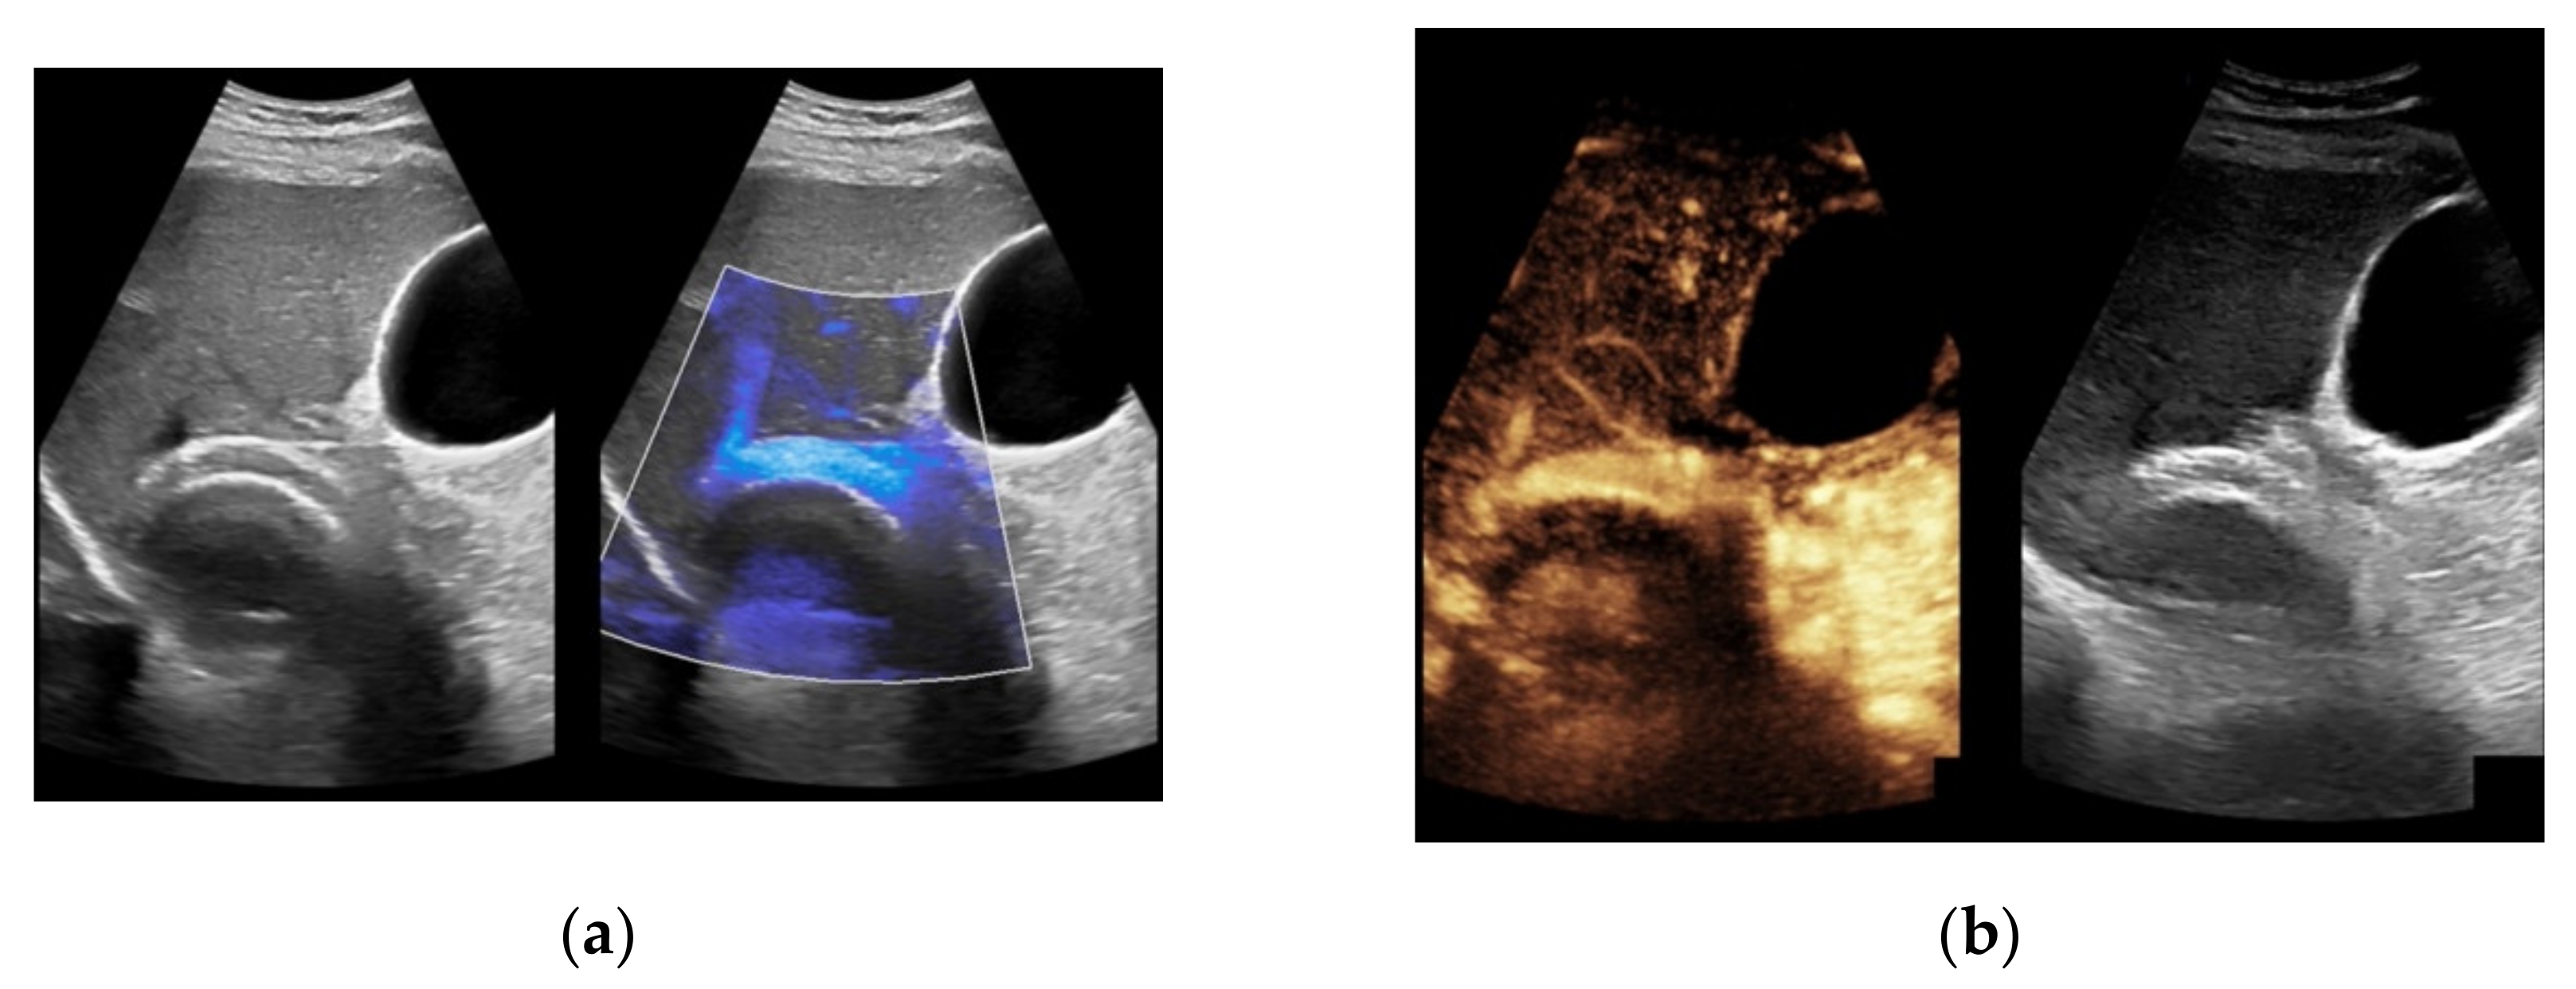

Figure 5. Same patient as in Figure 2. After administration of intravenous contrast, no intraluminal microbubbles can be registered within the transjugular intrahepatic portosystemic shunt compatible with complete occlusion (a,b).

Figure 6. Same patient as in Figure 3. Contrast-enhanced ultrasound shows partial flow signal within the transjugular intrahepatic portosystemic shunt with marginal hypoechoic areas within the stent indicating thrombotic depositions.